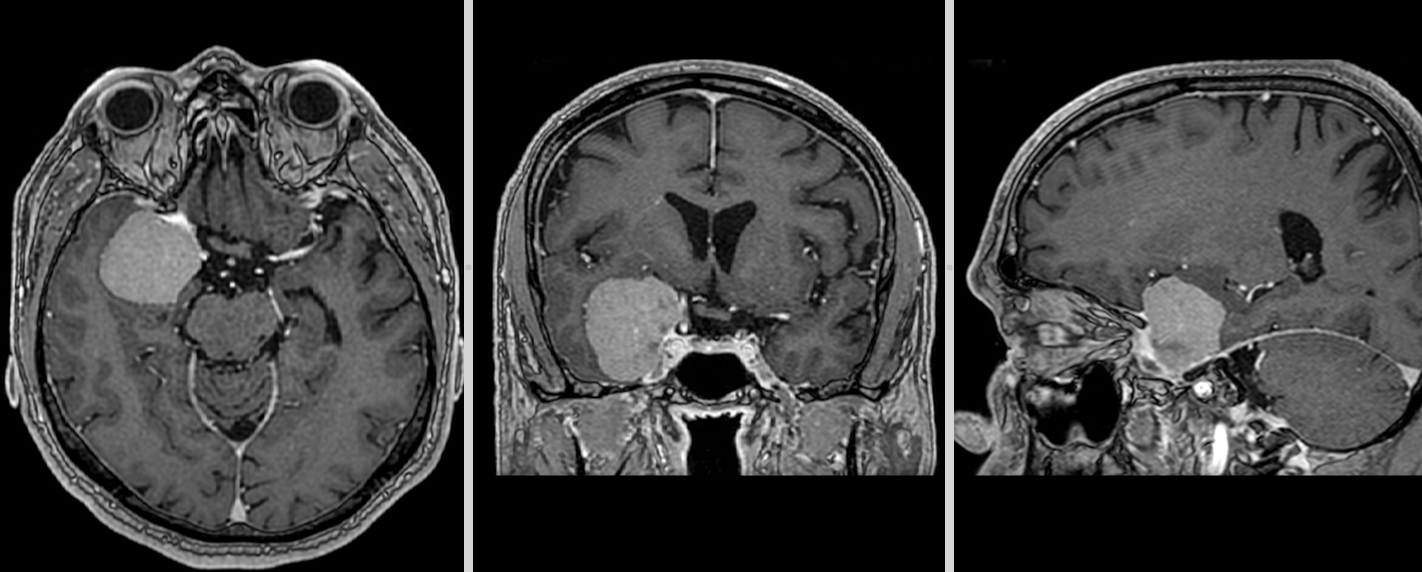

Meningiom de tubercul selar